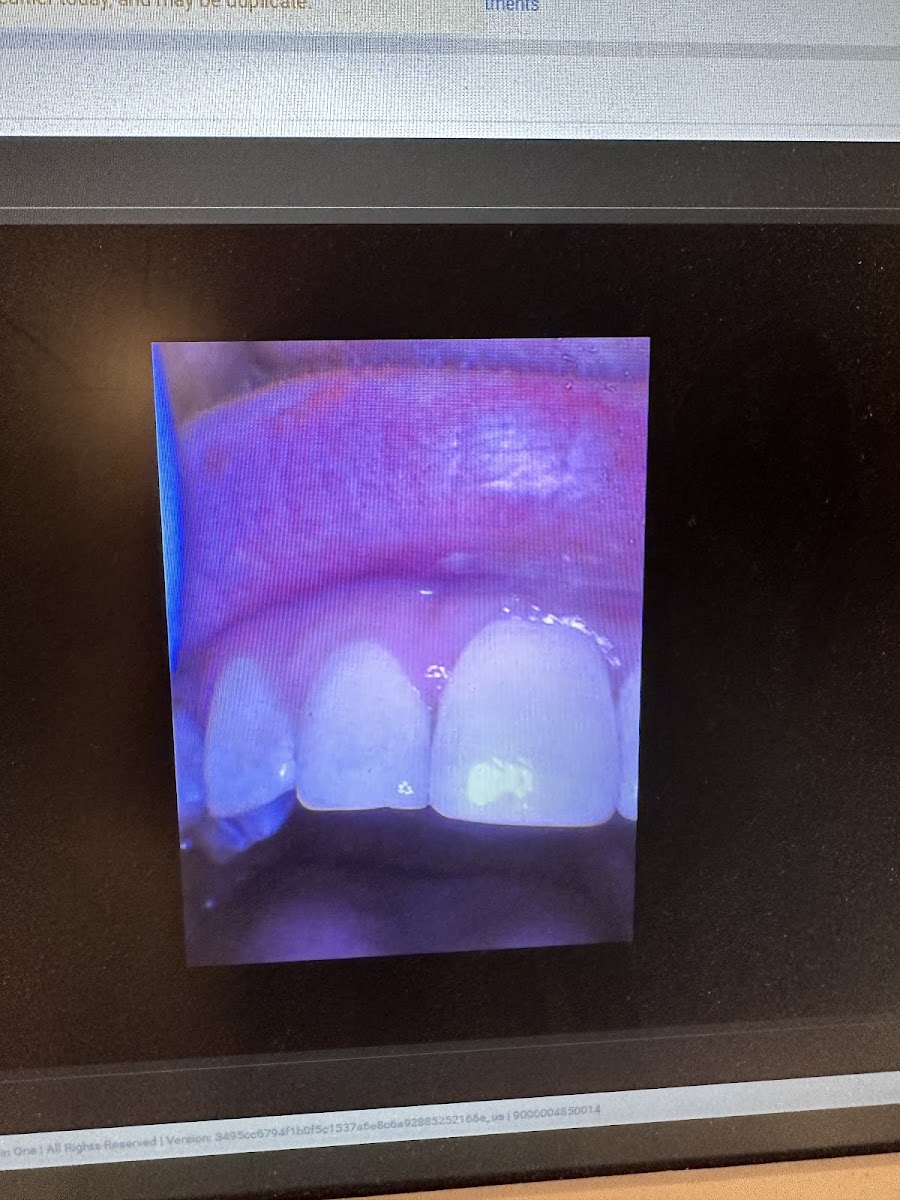

Shacore healed me of all of my dental related trauma. He gave me the best teeth cleaning ever. Before going to Tend, I would literally have to be sedated to go thru a regular teeth cleaning at my old family dentist. Shacore was gentle and explained every step he was doing which really put me at ease. At one point I almost fell asleep during the cleaning. Also, they show you photos of what your teeth looked like before the cleaning which was eye opening and helpful for me to see. Thank you Shacore for helping me overcome my fear of the dentist!